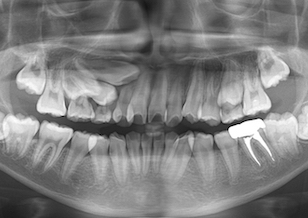

BeforeⅠは、治療前のパノラマレントゲンです。

レントゲン所見では、 右側上顎犬歯と第1小臼歯、第2小臼歯の3本が埋伏しております。右側上顎犬歯は隣の側切歯の歯根を圧迫し側切歯の歯根吸収を引き起こしており今後更なる歯根吸収の可能性が考えられました。

一般的には埋伏歯を放置しておいた場合、隣在歯の歯根吸収(歯冠が他の歯の歯根を圧迫することにより、歯根が溶けてしまうこと)が起こる場合があるので早めの対策が必要です。